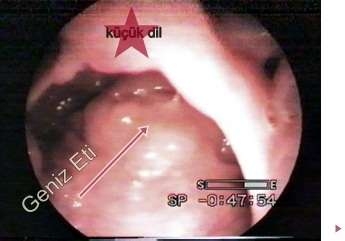

Ağzının arka üst kısmında yani burnun en arka nazofarenks denilen bölgedesinde yer alan dokulardır. Normalde bakıldığında görülmezler, görülmeleri için özel muayene yöntemi gerektirir. Geniz etleri endoskopik muayene , küçük muayene aynaları veya röntgen ile yöntemlerle görülebilir. Vücut için faydası olmayan lenf dokulardır. Genellikle çocuklarda bulunurlar. Burun etleri diye ifade edilen kavram burnun giriş kısmında bulunan ve fonksiyonu olan burun için faydalı organlardır. Genellikle geniz eti ile karıştırılır. Bunların farklı yapılar olduğu bilinmelidir.

Bademcikler (tonsil) dişlerinin arkasında boğaza bakıldığında küçük dilin iki yanında açıkça görülebilir;. Birlikte bağışıklık savunma görevini yaparlar, vücuda ana girişinde, soluduğumuz ve beslenirken alabileceğimiz olası mikroplara karşı yabancı işgalcilerden ilk korunma yoludur. Vücudun dokularının kalan aksine, bu yapılar çocukluk yaşlarının ortalarında en büyük boyut ulaşır ve daha sonra küçülerek sorun yaratmadan yerlerinde kalırlar. Geniz eti ve bademciklerin bu şekilde davranmaları, çocukların bulaşıcı hastalıklar dolu bir dünyada vücut savunmaları için gereklidir.